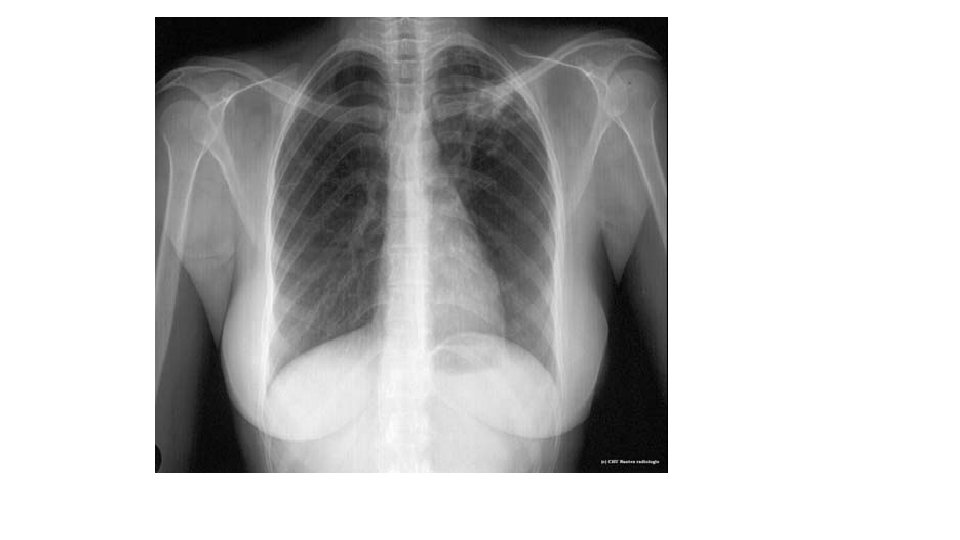

Définition • C’est l’ensemble des manifestations radiologiques témoignant d’une atteinte parenchymateuse( bronches, alvéoles, vaisseaux, interstitium) • Le siège parenchymateux est confirmé lorsque la lésion est entourée de tout part du parenchyme pulmonaire et lorsque son raccordement avec la paroi se fait en pente brusque (angle fermé)